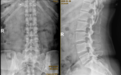

术前腰椎正侧位及动力位片